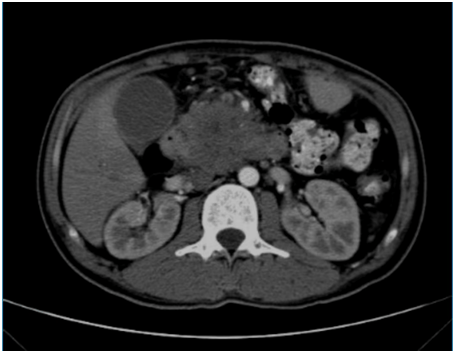

来源:磁共振成像传媒 截至2023年,膀胱癌是男性第四大癌症,占新发癌症的6%,占癌症相关死亡的4% 。组织病理学是肿瘤生物学中用于指导治疗的最可靠的决定因素之一 ,膀胱癌患者的治疗方案及预后评估在